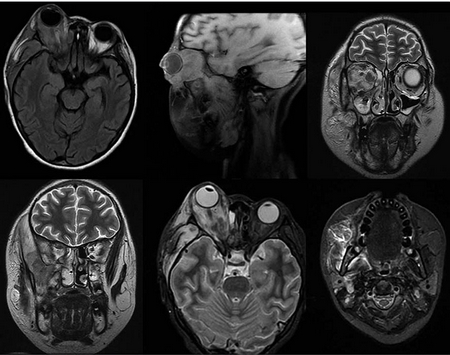

La ultrasonografía ocular reportó una lesión heterogénea que ejercía compresión y desplazamiento en sentido anterior del globo ocular derecho, y datos de inflamación de tejidos blandos (Figura 1). La tomografía computada describió la lesión como heterogénea e identificó datos de sinusitis y proptosis (Figura 2). Por resonancia magnética se reportó la misma lesión con aspecto heterogéneo de 5.5 ' 2.5 cm en sus diámetros mayores, que involucró tejidos musculares y con efecto de masa sobre estructuras orbitarias. No se observó extensión intracraneal, a cavidades paranasales ni al seno cavernoso (Figura 3). Ante una proptosis de rápida evolución y sospecha de probable rabdomiosarcoma se realizó biopsia transconjuntival de lesión intraconal y tejido peri-orbitario. Las preparaciones histológicas de la lesión intraconal y de la grasa orbitaria mostraron tejidos blandos con un proceso inflamatorio, necrótico con vasculitis de vasos de pequeño calibre con afección ocasional a vasos arteriales y venosos de mayor calibre. La vasculitis fue a expensas de linfocitos e histiocitos con trombosis aislada y algunos granulomas mal constituidos. El proceso inflamatorio estaba constituido por linfocitos, histiocitos, células plasmáticas y en una zona se mezclan con numerosos neutrófilos con cariorexis; la necrosis fue isquémica. Se realizaron diversas tinciones de histoquímica convencional e inmunohistoquímica para descartar neoplasia linfoide maligna o proceso infeccioso granulomatoso como micobacterias u hongos. La glándula lagrimal mostró afección por el proceso inflamatorio, la necrosis isquémica y la propia vasculitis. El diagnóstico fue de: granulomatosis de Wegener (Figura 4).

Figura 3 Resonancia magnética. Se observa una lesión intraorbitaria derecha, intra- y extraconal de aspecto heterogéneo, de 5.5 × 2.5 cm en sus diámetros mayores, que involucra al músculo recto externo, produciendo efecto de masa con proptosis y leve moldeamiento del globo ocular, desplazamiento del resto de estructuras musculares extraoculares, nervio óptico y glándula lacrimal, de aspecto hipointenso e hiperintensa en T1 y T2, con reforzamiento intenso y heterogéneo tras la administración de material de contraste con áreas que no reforzaron, sugestivas de necrosis. No se observa extensión intracraneal, ni a cavidades paranasales o a seno cavernoso.

Figura 6 Resonancia magnética. Se observa franco aumento de la lesión orbitaria derecha, con ampliación hacia espacio pterigopalatino, y afección de todos los músculos, incluyendo los pterigoideos, masetero y temporal derechos. En órbita se observan lesiones nodulares, con escaso contenido necrótico y con afección intra-craneal a nivel de meninges en región temporal del lado derecho, con reforzamiento casi homogéneo de la lesión, y escaso contenido necrótico. La pared posterior del antro maxilar y la cavidad nasal con franco engrosamiento de la mucosa. Además se observa involucro de la glándula parótida derecha.